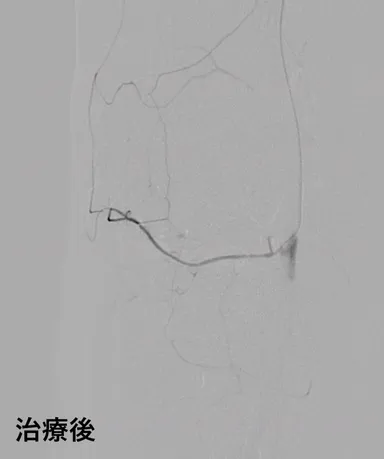

医療法人社団祐優会オクノクリニックは慢性的な痛みに悩む患者さんのために効果的な治療法を提案する、痛みの専門クリニックです。東京、横浜、大阪、神戸、札幌、仙台、福岡に計10医院を展開。痛みに悩む多くの患者さんと日々向き合っています。当院では月に約400人の患者さんが肩こり、五十肩、四十肩、腰痛、ひじ痛、膝痛、へバーデン結節の注射治療やカテーテルによる治療を行っています。カテーテルによる治療は、モヤモヤ血管が認められる痛みに効果的で、当院では今までに13,000人以上(※2017年10月~2022年8月当院調べ)の患者さんがカテーテル治療を受診しています。この運動器カテーテル治療は現在国内外で注目されており、当院にも海外からの多くの視察や受診依頼が来ています。